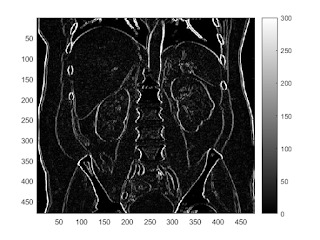

prewitt edge filter

b = fspecial('prewitt'); I2 = conv2(I,b.','same'); imagesc(abs(I2)); colorbar caxis([0,300])